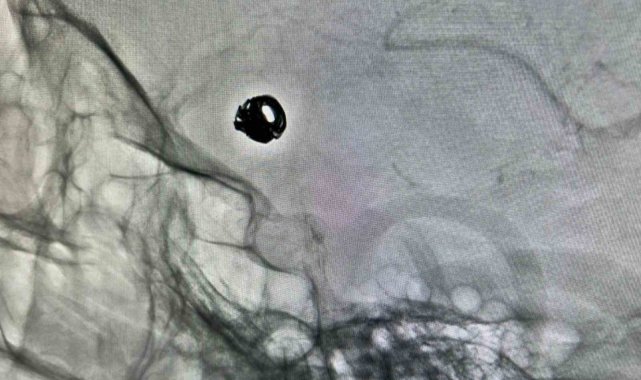

Bitlis Devlet Hastanesine bilinç bulanıklığı ve baş ağrısı şikâyetiyle başvuran 44 yaşındaki Sacide Derman, yapılan tetkiklerde beyin kanaması geçirdiği belirlenince ileri tedavi için Van Eğitim ve Araştırma Hastanesi'ne sevk edildi. Burada gerçekleştirilen anjiyografi sonucunda hastanın beyin damarlarında anevrizma (damar baloncuğu) tespit edildi. Girişimsel Radyoloji Merkezi'nde uygulanan kapalı anjiyografik yöntemle, kasıktan girilerek beyin damarlarına ulaşıldı ve anevrizma platin tel (coil) kullanılarak kapatıldı. İşlem sonrası takibi yapılan hastanın sağlık durumunun iyiye gittiği belirtildi.

Konuya ilişkin açıklama yapan Hastane Başhekimi Doç. Dr. Remzi Sarıkaya, her türlü komplike hastanın merkezlerine sevk edildiğini belirtti. Doç. Dr. Sarıkaya, "Hastamızın dış merkezde yapılan tomografi incelemesinde beyin kanaması ve beyin damarlarında anevrizma tespit edildi. Bunun üzerine hasta 112 ambulansı ile Van Eğitim ve Araştırma Hastanesi'ne sevk edildi. Kasıktan girilerek beyin damarlarına ulaşıldı ve endovasküler (kapalı yöntem) tedaviye uygun olduğuna karar verildi. Yaklaşık 1,5 saat süren işlemde, anevrizmanın içine platin teller (coil) yerleştirildi. Bu sayede baloncuğun kanla dolması engellenerek yeniden kanama ihtimali ortadan kaldırıldı" dedi.

Bitlis Devlet Hastanesi'ne baş ağrısı ve bilinç bulanıklığı şikâyetiyle başvuran hastanın daha sonra kendilerine sevk edildiğini aktaran Girişimsel Radyoloji Uzmanı Dr. Berat Demiral ise "Yapılan tomografi incelemesinde beyin kanaması tespit ediliyor. Ardından çekilen tomografik anjiyoda beyin damarlarında anevrizma (damar baloncuğu) tespit ediliyor. Bunun üzerine hasta, tedavi amacıyla 112 ambulansı ile Van Eğitim ve Araştırma Hastanesi'ne sevk ediliyor. Hastaya ilk olarak anjiyo işlemi yapıldı. Kasıktan girilerek beyin damarlarına özel kateterlerle ulaşıldı ve anevrizmanın endovasküler (kapalı yöntem) tedaviye uygun olduğuna karar verildi. Yaklaşık 1,5 saat süren işlemde, anevrizmanın ağzına mikrokateterle ulaşılarak içine platin teller (coil) yerleştirildi. Bu yöntemle baloncuğun kanla dolması engellendi ve yeniden kanama ihtimali ortadan kaldırıldı" diye konuştu.